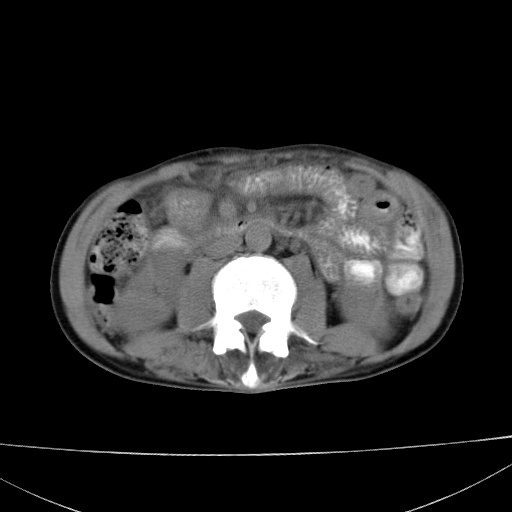

患者 男  41岁,右上腹痛伴腹泻10天,8年前有乙肝,本次b超查肝右叶占位来做ct ,请会诊!

肝硬化\\脾大\\门静脉高压,胃底静脉曲张可能性大.肝右叶肝癌肝内转移,建议增强.左侧小结石.

肝右叶肝癌肝内转移,建议增强

支持肝癌伴肝内转移,脾大,门静脉高压,胃底静脉曲张。

1)考虑肝癌;建议行ct增强扫描检查。2)脾大,门静脉高压,胃底静脉曲张。3)左肾小结石。

1)考虑肝癌及门脉瘤栓,建议行ct增强扫描检查。2)脾大,门静脉高压,胃底静脉曲张。3)左肾小结石。

结合病史;考虑肝癌。门静脉高压,脾大。胃底静脉曲张。

1)考虑肝癌;2)脾大,门静脉高压,胃底静脉曲张。3)左肾小结石。建议行ct增强扫描检查。